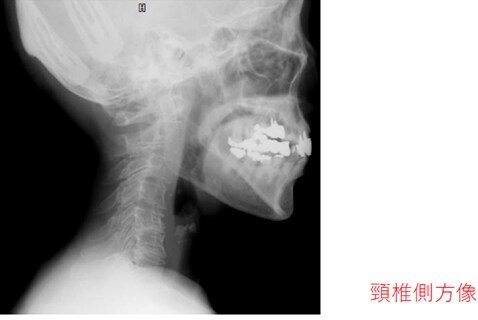

頚椎を横から撮影したレントゲンです。

こちらもラインを引いてみました。

理想の頚椎の並びは、

のど仏の方にせり出るようなカーブを描きます。

ストレートネックというより、

逆カーブを描いていますね。